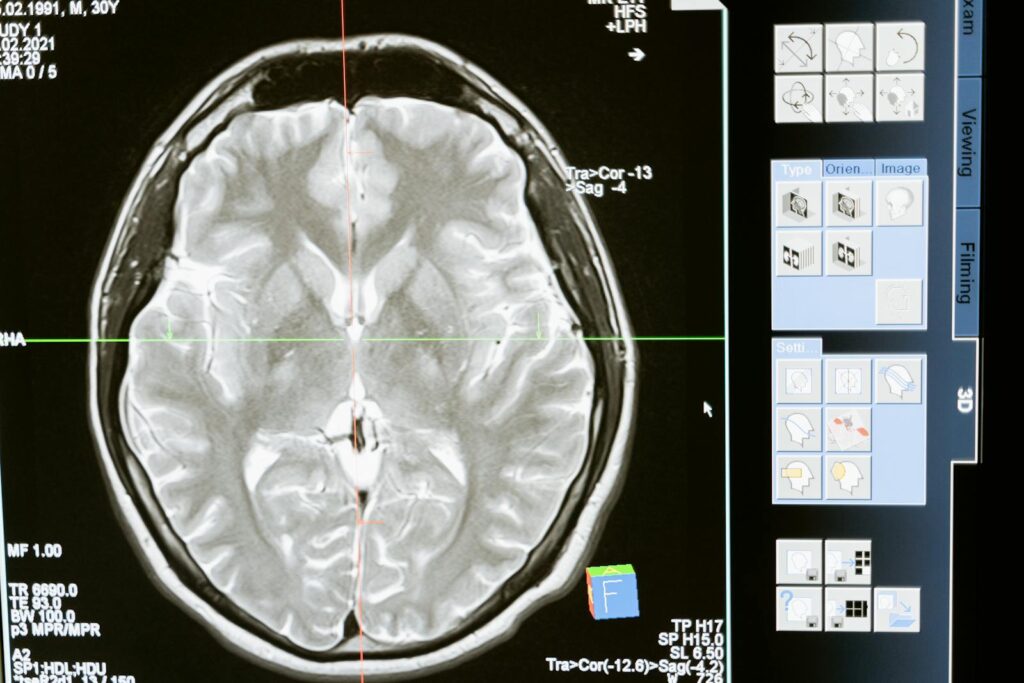

Something important happened in this field recently. Researchers at the University of Michigan published findings in 2024. They looked at brain recordings from four patients dying. These people were kept alive by machines. Brain waves were checked with a machine called an EEG. Dr. Jimo Borjigin’s team noticed something striking. Two patients showed a burst of brain activity right after the machines stopped. This final surge was seen in rats before; this was the first in humans, though.

This burst scene was quite interesting to them. It happened in the gamma wave frequency band. This band often connects to being conscious. The activity gathered where two brain parts meet, temporal and parietal. These areas matter a lot for processing conscious thoughts. Also, there were signs it linked to the front part of the brain more. That front part helps with thinking and choosing things. The scientists wrote the study strongly hinted the dying brain could be active. Dr. Charlotte Martial calls these findings really intriguing. She says they link the dying brain study to NDE research. She thinks this burst of activity might explain the strong experiences during NDEs.